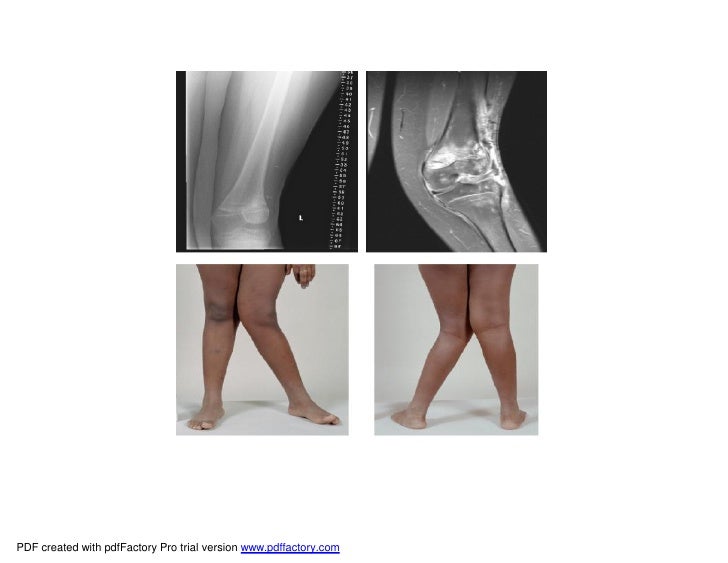

The Impact of Bone Deformity on Osteoarthritic Varus Knee Bone Deformity Calves Bowleg deformity is an incorrect alignment around the knee that can affect people of all ages. It is characterized by overly dense yet brittle bones that shatter easily. Congenital flexural deformities are seen within 1 or 2 weeks of birth. The condition is also known by. Calves that suffer from the mutation have deformed skulls, receding jaws, and protruding tongues.. Bone Deformity Calves.

top Excessive proximal varus, excessive distal valgus, internal tibial Bone Deformity Calves Known for providing stability to your lower leg and giving your calf its structure, the fibula is the longest, thinnest bone in the lower. It is characterized by overly dense yet brittle bones that shatter easily. Bowleg deformity is an incorrect alignment around the knee that can affect people of all ages. Calves that suffer from the mutation have deformed. Bone Deformity Calves.